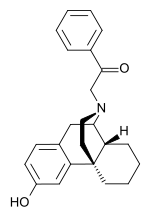

Morphinans

Morphinan series

Others

- 1-Nitroaknadinine * 14-episinomenine

- 5,6-Dihydronorsalutaridine

- 6-Keto Nalbuphine

- Aknadinine

- Butorphanol

- Cephakicine

- Cephasamine

- Cyprodime

- Drotebanol

- Fenfangjine G

- Ketorfanol

- Nalbuphine

- Nalbuphone

- Tannagine

Structures

| Other Morphinans | ||||

|---|---|---|---|---|

1-Nitroaknadinine 1-Nitroaknadinine |

14-episinomenine 14-episinomenine |

5,6-Dihydronorsalutaridine 5,6-Dihydronorsalutaridine |

6-Keto Nalbuphine 6-Keto Nalbuphine |

Aknadinine Aknadinine |

Butorphanol Butorphanol |

Cephakicine Cephakicine |

Cephasamine Cephasamine |

Cyprodime Cyprodime |

Drotebanol Drotebanol |

Fenfangjine G Fenfangjine G |

Nalbuphine Nalbuphine |

Sinococuline Sinococuline |

Sinomenine Sinomenine |

Tannagine Tannagine |